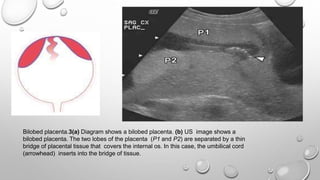

Bilobed placenta.3(a) Diagram shows a bilobed placenta. (b) US image shows a

bilobed placenta. The two lobes of the placenta (P1 and P2) are separated by a thin

bridge of placental tissue that covers the internal os. In this case, the umbilical cord

(arrowhead) inserts into the bridge of tissue.